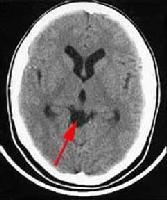

+Chụp cắt lớp vi tính (CT Scanner) não tìm các hình ảnh đặc hiệu (các nang sán là những nốt dịch có chấm mờ, kích thước 3-5mm, đôi khi nang có kích thước lớn đến 10mm, rải rác có nốt dạng vôi hóa);